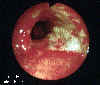

Ischemic colitis

A case of stricture type ischemic colitis recognized 5 years after an operation for advanced rectal cancer.

Tokyo Pref., Cooperative study between National Cancer Center and Kyushu Cancer Center

Endoscopy

Inflammatory or ulcerative disease / lesions/Ischemic colitis